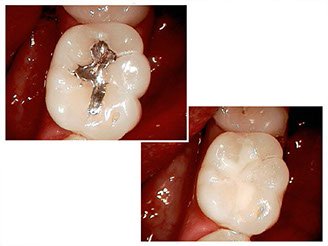

Root canal treatment

Advances in the field of root canals have led to effective, consistent, and predictable results.

Why do people need them?

Treating a tooth with a root canal involves removing and shaping the inner portion of a tooth, cleaning and disinfecting the root canal spaces, and filling the roots.

Successful treatment of a complicated molar with four canals by Dr. Young